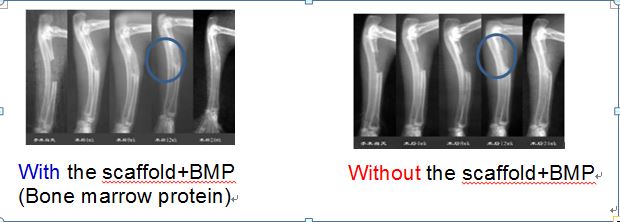

동물분야에서도 줄기세포, 재생의학, 3D 바이오 프린팅 등 변화의 물결이 전 세계적으로 빠르게 불고 있다. 골절상의 경우 PLA+b TCP를 융합한 합성골에 BMP(Bone Marrow Protein)을 프린팅 해 회복기간을 1/2로 줄인 신치료법은 지난 수년 동안 수많은 동물 임상을 통해 입증되고 있다.